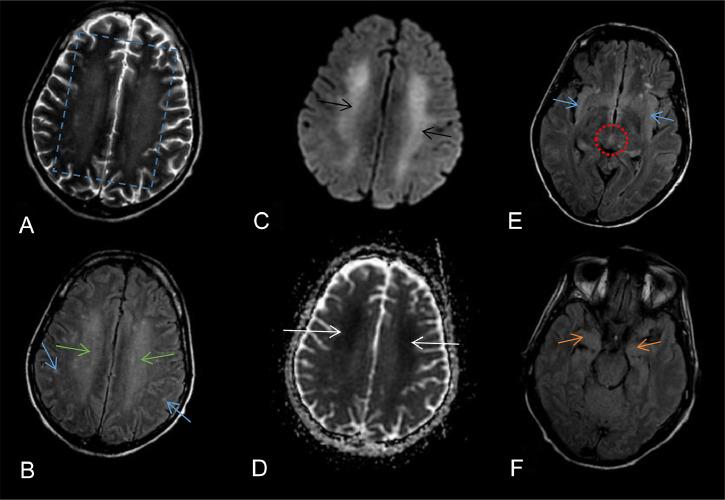

Paraneoplastic encephalomyelitis (PEM) is a rare complication associated with malignancies, often presenting before the cancer diagnosis. A 42-year-old male with a history of chronic smoking presented with acute urinary retention and neurological deficits, all evolving in a febrile context with general deterioration. Laboratory tests were conducted, followed by a cerebral MRI which revealed multiple T2 and FLAIR hyperintense lesions in the periventricular and periaqueductal regions, medial temporal lobes, and bilateral postero-medial thalamus. Enhanced CT scans of the chest and abdomen identified multiple cervical, axillary, and inguinal lymphadenopathies. Subsequently, an ultrasound-guided biopsy of a cervical node was performed. His condition deteriorated rapidly, requiring intubation and sedation. A subsequent MRI revealed worsening cerebral and spinal cord lesions with new contrast enhancement in the brainstem. The differential diagnosis included toxic/metabolic and paraneoplastic causes. Biopsy results confirmed Hodgkin's lymphoma, leading to a diagnosis of progressive paraneoplastic encephalomyelitis (PEM). Despite adequate treatment, the patient's condition worsened, leading to death from pneumonitis and metabolic complications. This case underscores the importance of considering PEM in patients with neurological deficits and malignancy, with MRI playing a crucial role in diagnosis. Early detection and treatment are essential to improving outcomes.

摘要

副肿瘤性脑脊髓炎(PEM)是一种与恶性肿瘤相关的罕见并发症,通常在癌症诊断之前出现。一名有长期吸烟史的42岁男性,出现急性尿潴留和神经功能缺损,所有症状均在发热背景下逐渐发展并伴有全身状况恶化。进行了实验室检查,随后进行了脑部MRI检查,结果显示脑室周围和导水管周围区域、颞叶内侧以及双侧丘脑后内侧出现多个T2加权像和液体衰减反转恢复序列(FLAIR)高信号病变。胸部和腹部增强CT扫描发现多个颈部、腋窝和腹股沟淋巴结肿大。随后,对一个颈部淋巴结进行了超声引导下活检。他的病情迅速恶化,需要插管和镇静。随后的MRI显示脑和脊髓病变恶化,脑干出现新的强化。鉴别诊断包括中毒/代谢性和副肿瘤性病因。活检结果确诊为霍奇金淋巴瘤,从而诊断为进行性副肿瘤性脑脊髓炎(PEM)。尽管进行了充分治疗,患者的病情仍恶化,最终因肺炎和代谢并发症死亡。该病例强调了在有神经功能缺损和恶性肿瘤的患者中考虑PEM的重要性,MRI在诊断中起着关键作用。早期检测和治疗对于改善预后至关重要。